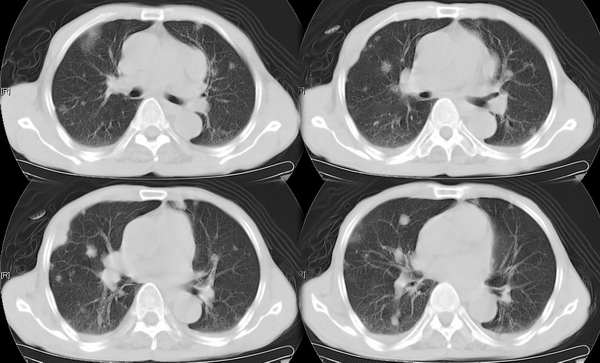

右颈部巨大软组织肿块影,范围较广,上至下颌角,下至颈静脉切迹。其最大层面位于右侧甲状腺区。肿块密度不均,其中有坏死液化区和班片状钙影,增强扫描见肿块实质区有强化。邻近结构挤压移位,部分结构侵蚀破坏,右侧多个颈深淋巴结肿大。两肺弥漫分布小结节影,以胸膜下为主,其大小不等,边缘光整。右侧胸壁亦见软组织结节影,纵隔多个淋巴结肿大及两侧锁骨上淋巴结肿大。

意见:右侧甲状腺癌并两肺、胸壁、纵隔淋巴结、颈深淋巴结、锁骨上淋巴结等广泛转移。